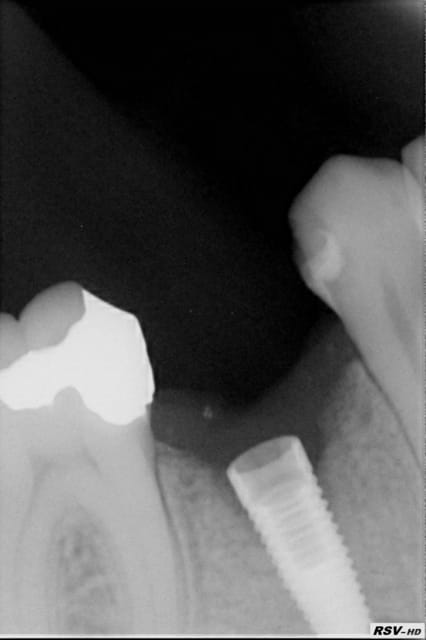

Implant en nourrice depuis 2 mois dans un site dont l'alvéole a été comblée avec du Btcp + membrane sockette Zimmer mais "betise" j'ai oublié la vis de couverture..... Le substitut osseux a été laissé 6 mois. A l'examen en bouche, tout est OK, mais voici l'image radio.

Qu'en pensez-vous ? et quelle conduite me conseillez-vous ?

c'est à dire que ce qui est le plus préoccupant pour la suite c'est pas cette absence de vis de couverture mais plutôt la perte osseuse péri-implantaire et en trouver la raison me semble être interessant.

je suis bien d'accord avec toi...mais l'absence même de la vis de couverture peut aussi être la raison de l'état péri implantaire actuel...(pénétration alimentaire par exemple, entretenant un "pseudo" foyer infectieux...)

oui pluton , ce qui m'interesse c'est justement de savoir si une absence de vis de cicatrisation peut à elle seule provoquer une inflammation péri-implantaire. Dans l'absolu je ne vois pas trop comment si au départ la plaie est suturée bien hermétiquement. Il est probable que l'absence de vis permettent dans les tous premiers temps une pénétration bactérienne dans le fût qui maintienne par la suite une toute petite oprerculisation peu visible?

Implant anthogyr a col non fileté mais rugueux (anthofit full bcp )

un tissu granuleux pourrait avoir gagné le fut implantaire en 1er et le col ensuite????Si,la gencive kératinisée présente a l'aplomb du col un petit tatouage d'un petit mm de diam. ????

Question surement stupide :pourrait il y avoir un lien avec l'utilisation de béta TCP de comblement alvéolaire et le traitement de surface de ce type d'implant au BCP???